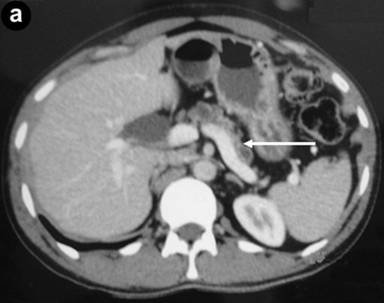

A 35-year-old male suffered from colicky abdominal pain in the right hypochondrium and epigastrium of four months duration, not associated with jaundice or weight loss. On admission, his total bilirubin was 0.7 mg/dL, AST 23 IU/L, ALT 15 IU/L, alkaline phosphatase 104 IU/L, GGT 9 IU/L and amylase 112 IU/L (reference ranges: 0-110 IU/L). A CT scan showed atrophy of the pancreas with a 1 cm dilatation of the pancreatic duct (Figure 3a). A calculus was seen in the pancreatic duct near the ampulla (Figure 3b). Diffuse dilatation of the common hepatic duct and the common bile duct was seen without any calculus, suggestive of a choledochal cyst. MRCP confirmed this finding and also showed significant atrophy of the pancreas; a pancreatic duct 1 cm in diameter (Figure 4) and an isointense filling defect was seen in the pancreatic duct at its distal end near the ampulla. A diagnosis of chronic calcific pancreatitis with type I choledochal cyst was made. He underwent choledochal cyst excision with a cholecystectomy, hepaticojejunostomy (end-to-side) and side-to-side pancreaticojejunostomy. Tissue from the head of the pancreas confirmed the diagnosis of chronic pancreatitis. Surgery and recovery were uneventful. He is asymptomatic after a 4 month follow-up.

Figure 3. CT showing atrophic pancreas with a dilated (1 cm) pancreatic duct (a. arrow) and calcification at the head and uncinate process of the pancreas (b.). |